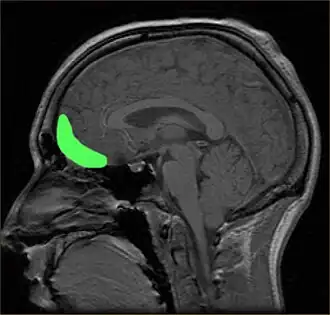

The visual brain segregates visual elements like luminance, color, and motion, as well as higher order objects like faces, bodies, and landscapes. Aesthetic encounters engage these sensory systems. For example, gazing at Van Gogh's dynamic paintings evokes a subjective sense of movement and activates visual motion areas V5/MT+.[32] Portraits activate the face area in the fusiform gyrus (FFA) and landscape paintings activate the place area in the parahippocampal gyrus (PPA).[33] Beyond classifying visual elements, these sensory areas may also be involved in evaluating them. Beautiful faces activate the fusiform face and adjacent areas.[34] The question of how much and what kind of valuation takes place in sensory cortices is an area of active inquiry.

The prefrontal cortex is previously known for its roles in the perception of colored objects, decision making, and memory. Recent studies have also linked it to the conscious aesthetic experience because it is activated during aesthetic tasks such as determining the appeal of a visual stimuli. This may be because a judgment is needed, requiring visiospatial memory. In a study performed by Zeki and Kawabata, it was found that the medial orbito-frontal cortex (mOFC) is involved in the judgment of whether a painting is beautiful or not.[44] There is high activation in this region when a person views paintings which they consider beautiful. Other evidence shows that this same area is active during the experience of beauty derived from different sources,[55] including musical beauty[56] and moral beauty,[57] and even mathematical beauty.[58] Experience of the sublime, as opposed to the beautiful, results in a different pattern of brain activity;[59] moreover, where it comes to judgment, although aesthetic and perceptual judgments leads t activity in the same brain areas, the pattern of activity is also different between the two, one of the most marked differences being the involvement of mOFC in aesthetic, but not in perceptual, judgments.[60] Surprisingly, when a person views a painting which they consider ugly, no separate structures are activated. Therefore, it is proposed that changes in the intensity of activation in the orbito-frontal cortex correlate with the determination of beauty (higher activation) or ugliness (lower activation).

Additionally, the prefrontal dorsalateral cortex (PDC) is selectively activated only by stimuli considered beautiful whereas prefrontal activity as a whole is activated during the judgment of both pleasing and unpleasing stimuli.[8] The prefrontal cortex may be generally activated for directing the attention of the cognitive and perceptual mechanisms towards aesthetic perception in viewers untrained in visual arts.[23] In other words, related directly to a person viewing art from an aesthetic perception due to the top-down control of their cognition. The lateral prefrontal cortex is shown to be linked to higher order self-referential procession and the evaluation of internally generated information. The left lateral PFC, Brodmann area 10, may be involved in maintaining attention on the execution of internally generated goals associated with approaching art from an aesthetic orientation.[23]

Emotions play a large role in aesthetic processing. Experiments designed specifically to force the subjects to view the artwork subjectively (by inquiring of its aesthetic appeal) rather than simply with the visual systems, revealed a higher activation in the brain's emotional circuitry. Results from these experiments revealed high activation in the bilateral insula which can be attributed to the emotional experience of viewing art.[23] This correlates with other known emotional roles of the insula. However, the correlation between the insula's varying states of activation and positive or negative emotions in this context is unknown. The emotional view of art can be contrasted with perception related to object recognition when pragmatically viewing art. The right fusiform gyrus has been revealed to show activation to visual stimuli such as faces and representational art.[23] The neuroaesthetics of facial recognition hold particular importance, as being drawn to faces likely increased sociability, allowing tribal environments to grow, resulting in greater protection and more availability of mates.[61] This is likely involved in genetic fitness of offspring and child-rearing as well.

This holds importance in the field because as Ramachandran also speculated, object recognition and the search for meaning can evoke a pleasant emotional response. The motor cortex was also shown to be involved in aesthetic perception. However, it displayed opposite trends of activation from the OFC.[44] It may be a common correlate for the perception of emotionally charged stimuli despite its previously known roles. Several other areas of the brain were shown to be slightly activated during certain studies such as the anterior cingulate cortex,[23][44] previously known for its involvement in the feeling of romance, and the left parietal cortex, whose purpose may be to direct spatial attention.[44]